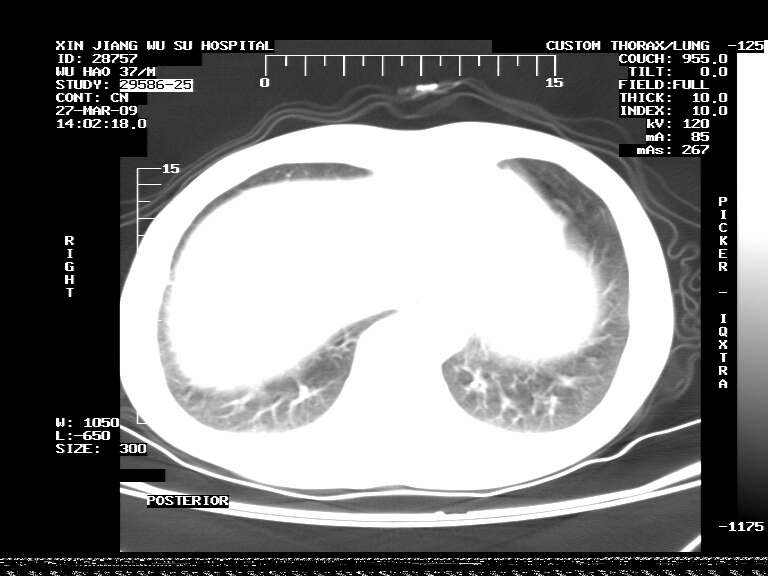

男,37岁,体检胸透发现阴影。

患者体检发现 无症状 左肺下叶占位,边缘模糊,可见血管聚束、分叶、胸膜牵拉,增强呈不均匀性强化。 首先考虑左肺下叶周围型肺癌,建议穿刺活检。

患者体检发现 无症状 左肺下叶占位,边缘模糊,可见血管聚束、分叶、胸膜牵拉,增强呈不均匀性强化。 首先考虑左肺下叶周围型肺癌,建议穿刺活检。支持!

左肺下叶见一结节病变,边缘欠清不光滑,与胸膜粘连且胸膜局限性增厚,注药后呈环形强化,动脉期壁呈明显点环状强化,静脉期壁强化减低,中心密度低无强化,灶周无明显的卫星灶和水肿区(晕征)---考虑周围性肺癌,不除外感染性病变,建议穿刺活检。

左肺下叶结节影.密度不均,边缘不规则.周围少许渗出.考虑感染性病变.结核?肿瘤待排.

左肺下叶软组织病灶,密度较高,内见点状钙化,其周围见子灶,邻近胸膜扁平样增厚.c+病灶强化明显,中心强化弱.诊断:左肺下叶结核瘤.

左肺下叶大片实变影,内靠胸膜见不规则更高密度结节灶,边缘强化,相邻胸膜增厚,胸膜下脂肪线存在。考虑炎症,结核可能。